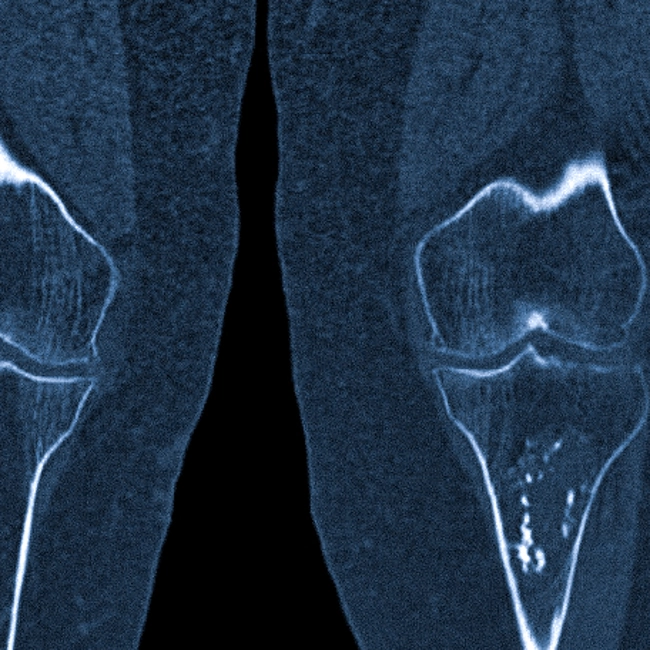

| Компьютерная томография (КТ) | Является «золотым стандартом» диагностики остеоид-остеомы. КТ с высокой точностью визуализирует маленькое гнездо опухоли и зону склероза вокруг него. | Позволяет безошибочно подтвердить диагноз, определить точные размеры и расположение гнезда, что критически важно для планирования лечения. |

| Магнитно-резонансная томография (МРТ) | Хорошо показывает реакцию окружающих мягких тканей и костного мозга — отек и воспаление. Само гнездо на МРТ может быть видно не так четко, как на КТ. | Используется для дифференциальной диагностики с другими заболеваниями, особенно со злокачественными опухолями или остеомиелитом. |